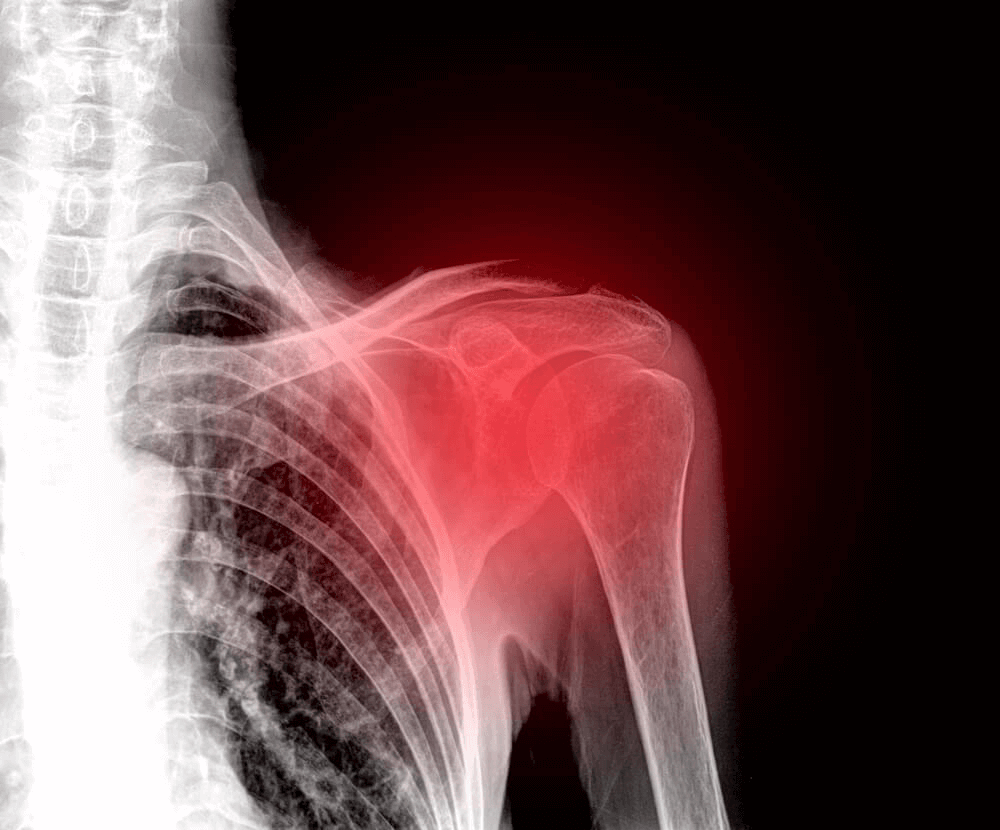

La rupture de la coiffe des rotateurs est une pathologie qui affecte très souvent l’épaule chez les personnes d’âge moyen. C’est l’une des principales causes de douleurs à l’épaule aujourd’hui.

Malheureusement, l’épaule est une partie du corps qui a tendance à souffrir et à causer de nombreux inconforts. En réalité, une blessure dans cette région est très invalidante et douloureuse. C’est pourquoi cet article explique tout ce que vous devez savoir sur la rupture de la coiffe des rotateurs.

Tout d’abord, pour diagnostiquer la rupture de la coiffe des rotateurs, le médecin procédera à un examen physique. Au cours de cet examen, le médecin examinera la capacité de bouger, la force et la douleur dans l’articulation.

Des examens complémentaires tels que l’échographie ou l’IRM sont souvent utilisés. L’échographie permet d’évaluer les tendons et les muscles pendant le mouvement. C’est aussi un test abordable et non invasif.